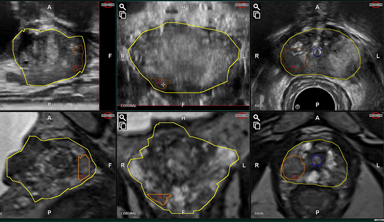

USとMRIによる前立腺輪郭のオーバーラップ

自動弾性 (Elastic) フュージョン

Adoptモード

(手動位置ずれ補正)

自動輪郭追従モード

(前立腺の動きをリアルタイムで追従)

前立腺、病変、尿道

3D立体モデル (4画面)